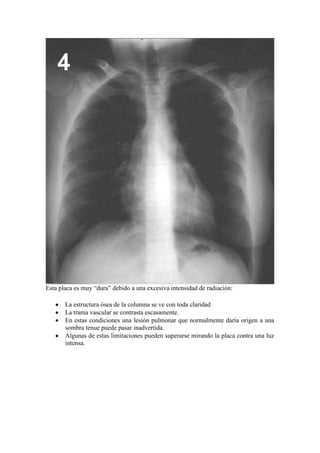

Esta placa es muy “dura” debido a una excesiva intensidad de radiación:

La estructura ósea de la columna se ve con toda claridad

La trama vascular se contrasta escasamente.

En estas condiciones una lesión pulmonar que normalmente daría origen a una

sombra tenue puede pasar inadvertida.

Algunas de estas limitaciones pueden superarse mirando la placa contra una luz

intensa.